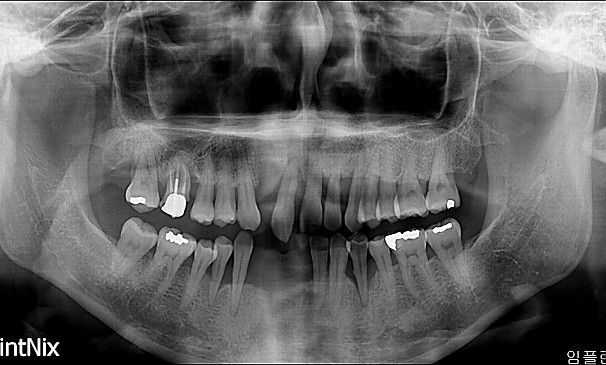

명OO님 전후사진 | 치료 기간 : 30

치료 전

치료 후